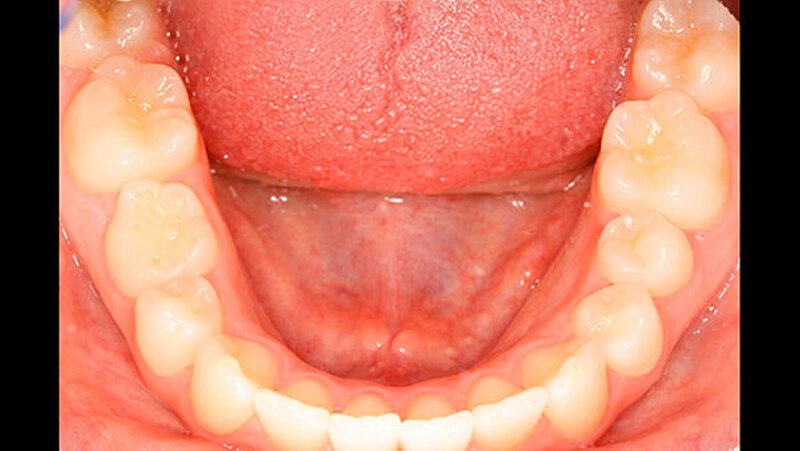

An Zahn 11 zeigte sich im inzisalen Drittel zusätzlich eine runde Schmelzopazität mit geringfügiger Hypoplasie (Abbildung 3), beides waren die Folge eines Frontzahntraumas im Milchgebiss. Darüber hinaus befand sich im zervikalen Drittel des gleichen Zahns eine rillenförmige Hypoplasie im Schmelz, höchstwahrscheinlich durch denselben Unfall verursacht (Abbildung 3).